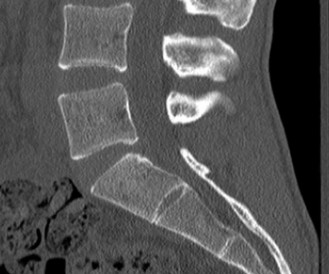

Upon his return five years later, the imaging profile was drastically different. Standing lateral radiographs now revealed a Meyerding Grade 2 spondylolisthesis at L5-S1, indicating that the L5 vertebral body had translated anteriorly by 25% to 50% over the sacral promontory. Furthermore, there was a noticeable collapse of the L5-S1 intervertebral disc space, signifying advanced degenerative changes secondary to the altered biomechanics and chronic instability. We also meticulously measured the patient's spinopelvic parameters on a standing 36-inch scoliosis cassette. His Pelvic Incidence (PI) was measured at 65 degrees (high), which mathematically dictates a higher Sacral Slope (SS) and Pelvic Tilt (PT). A high PI is a known biomechanical risk factor for the progression of spondylolisthesis, as it creates a steeper lumbosacral shear angle, placing immense anterior translational force across the compromised L5-S1 segment.

Clinical & Radiographic Imaging Archive